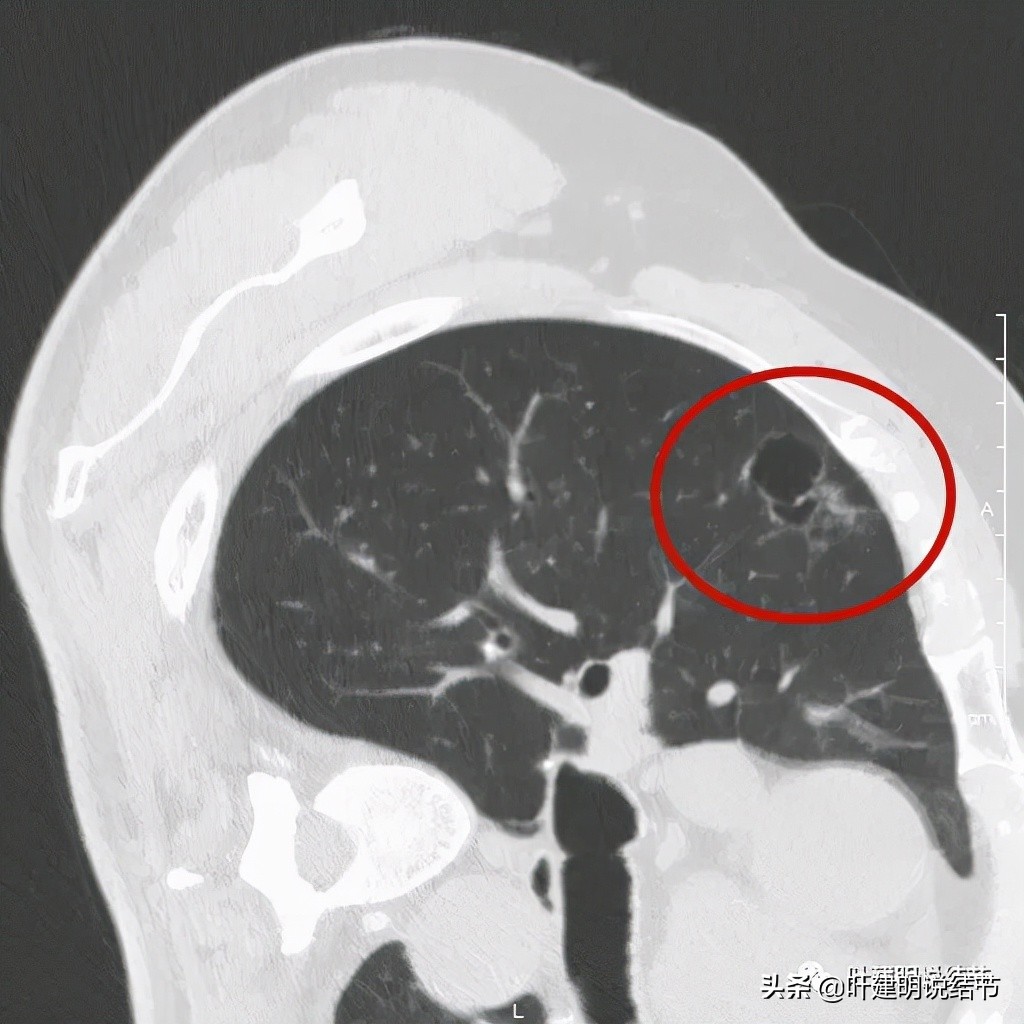

以上诸图是病灶4:考虑囊腔型肺癌可能性大,壁厚薄不均,内壁不光滑,有血管进入病灶,有少许密度偏高的成分,但纵隔窗上未见,不是真正意义上的实性成分。